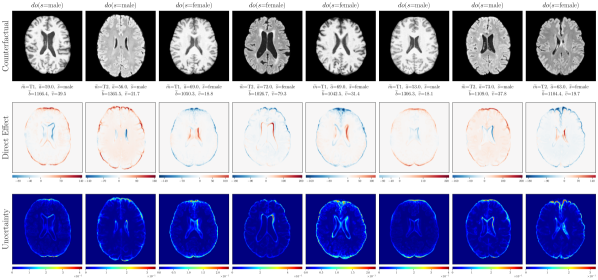

4.2 Brain Imaging Counterfactuals

To demonstrate our model’s ability to produce faithful high-fidelity counterfactuals of real data, we extend our approach to a real-world scenario involving brain MRI scans from the UK Biobank (Sudlow et al., 2015). As before, we start with an assumed causal generative process involving a set of observed variables as shown in Figure 4(a). The causal graph is medically informed and extends the scenario in Pawlowski et al. (2020) by: (i) introducing an additional MRI Sequence (T1/T2) binary variable to enable discrete counterfactuals; (ii) having directly. We used a scaled-up version of our exogenous prior HVAE as ’s mechanism and used (conditional) normalizing flows for the other mechanisms (see Appendix A.1). As shown in Figure 4, our deep SCM is capable of producing qualitatively sharp counterfactuals with localised changes according to the intervened upon parent(s) and the associated causal graph. Importantly, the identity of subjects is well preserved in all cases including null-interventions (i.e. nothing). Table 2 shows the counterfactual effectiveness results from random interventions on each variable. We observed satisfactory initial counterfactual effectiveness and significant improvements of post counterfactual training, demonstrating the merit of the proposed approach. Please refer to Appendix A.2 for notes on abduction uncertainty and D for additional results.

D.3 Extra Results

‘MRI Seq.’ counterfactuals

Post counterfactual training:

‘Sex’ counterfactuals

‘Age’ counterfactuals

‘Brain Volume’ counterfactuals

‘Ventricle Volume’ counterfactuals